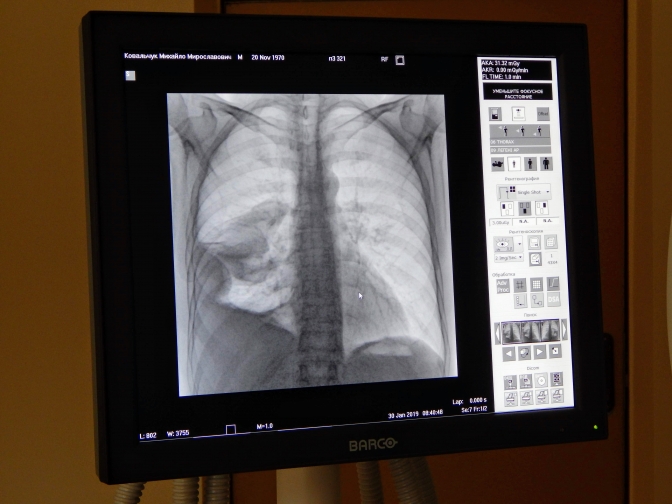

На Львівщині у Дрогобичі не працює жоден комп’ютерний томограф. Цей апарат визначає, чи вражені легені людини коронавірусом.

“Дожилися: Дрогобич впевнено рухається до червоної зони карантину, але на сьогодні в багатотисячному за населенням місті не працює жоден КТ (комп’ютерний томограф)”, – йдеться у повідомленні.